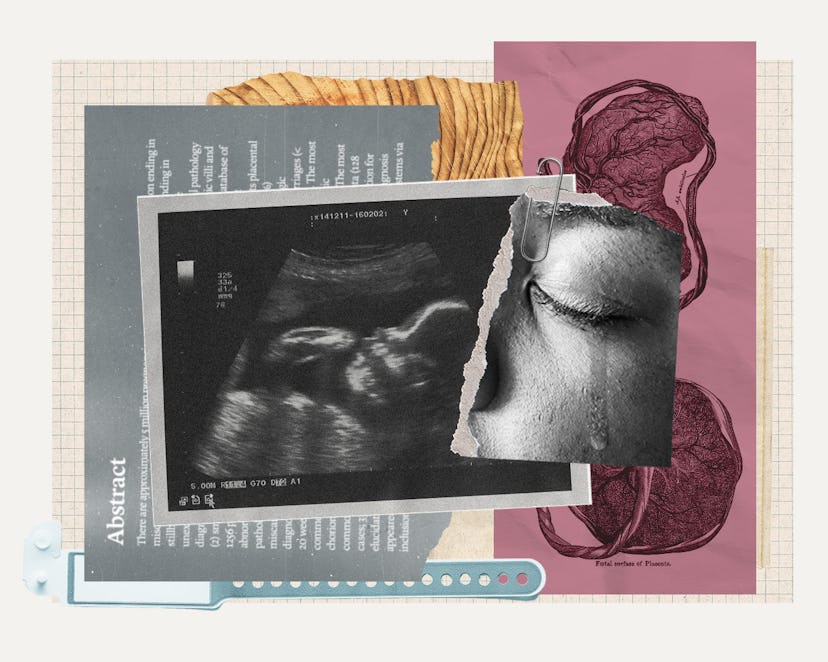

If This Pregnancy Screening Could Prevent 30% Of Stillbirths, Why Is No One Using It?

It was the summer of 2018, and Ann O’Neill was pregnant with her fourth baby — another boy. By all standards, this pregnancy, like her others, was healthy and low risk. On the morning before her due date, she noticed her baby had stopped moving. She didn’t want to be perceived as the “stereotypical, hysterical pregnant woman,” but she headed to the hospital anyway, just to be safe. It was there that a doctor told her her baby no longer had a heartbeat.

O’Neill delivered her son, Elijah, the following day. He was born at 8 pounds and 13 ounces, and the OB-GYN could not explain why he had died. “I was terrified initially to look for answers," O’Neill told me, but she requested an autopsy, genetic testing, and for labs to be run on her placenta. “I thought for sure I had done something wrong, but I didn’t know what. I didn’t eat lunch meat. I didn’t change kitty litter. I thought I had followed all the rules. He died and I was the one caring for him, so I thought it must be my fault.”

Three months and one long, confusing pathology report later, there was still no clear explanation for Elijah’s death. Then, in mid-October 2018, just weeks after receiving the fruitless pathology report, O’Neill’s ears perked up while she was listening to a podcast called Stillbirth Matters. A placental pathologist was explaining that small placentas can cause a stillbirth. He claimed that about a third of stillbirths could be prevented with a simple new screening tool he had developed through his work as the director of the Reproductive Placental Research Unit at the Yale School of Medicine.

Elijah had had a very, very small placenta, O’Neill remembered. The pathology report said it was below the 10th percentile. Why had no one checked her placenta size during her pregnancy? O’Neill immediately reached out to the podcast guest, Dr. Harvey J. Kliman, M.D., Ph.D.